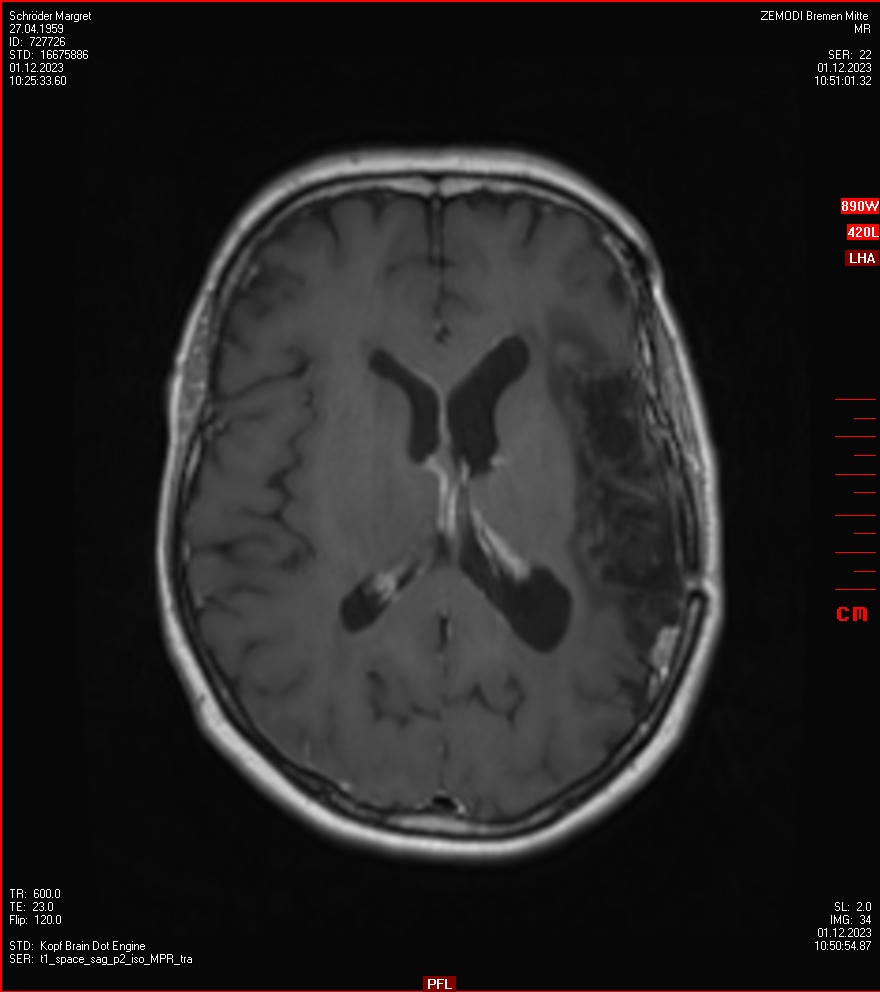

Zum Vergleich nun auch die Bilder vom 1.12.2023: